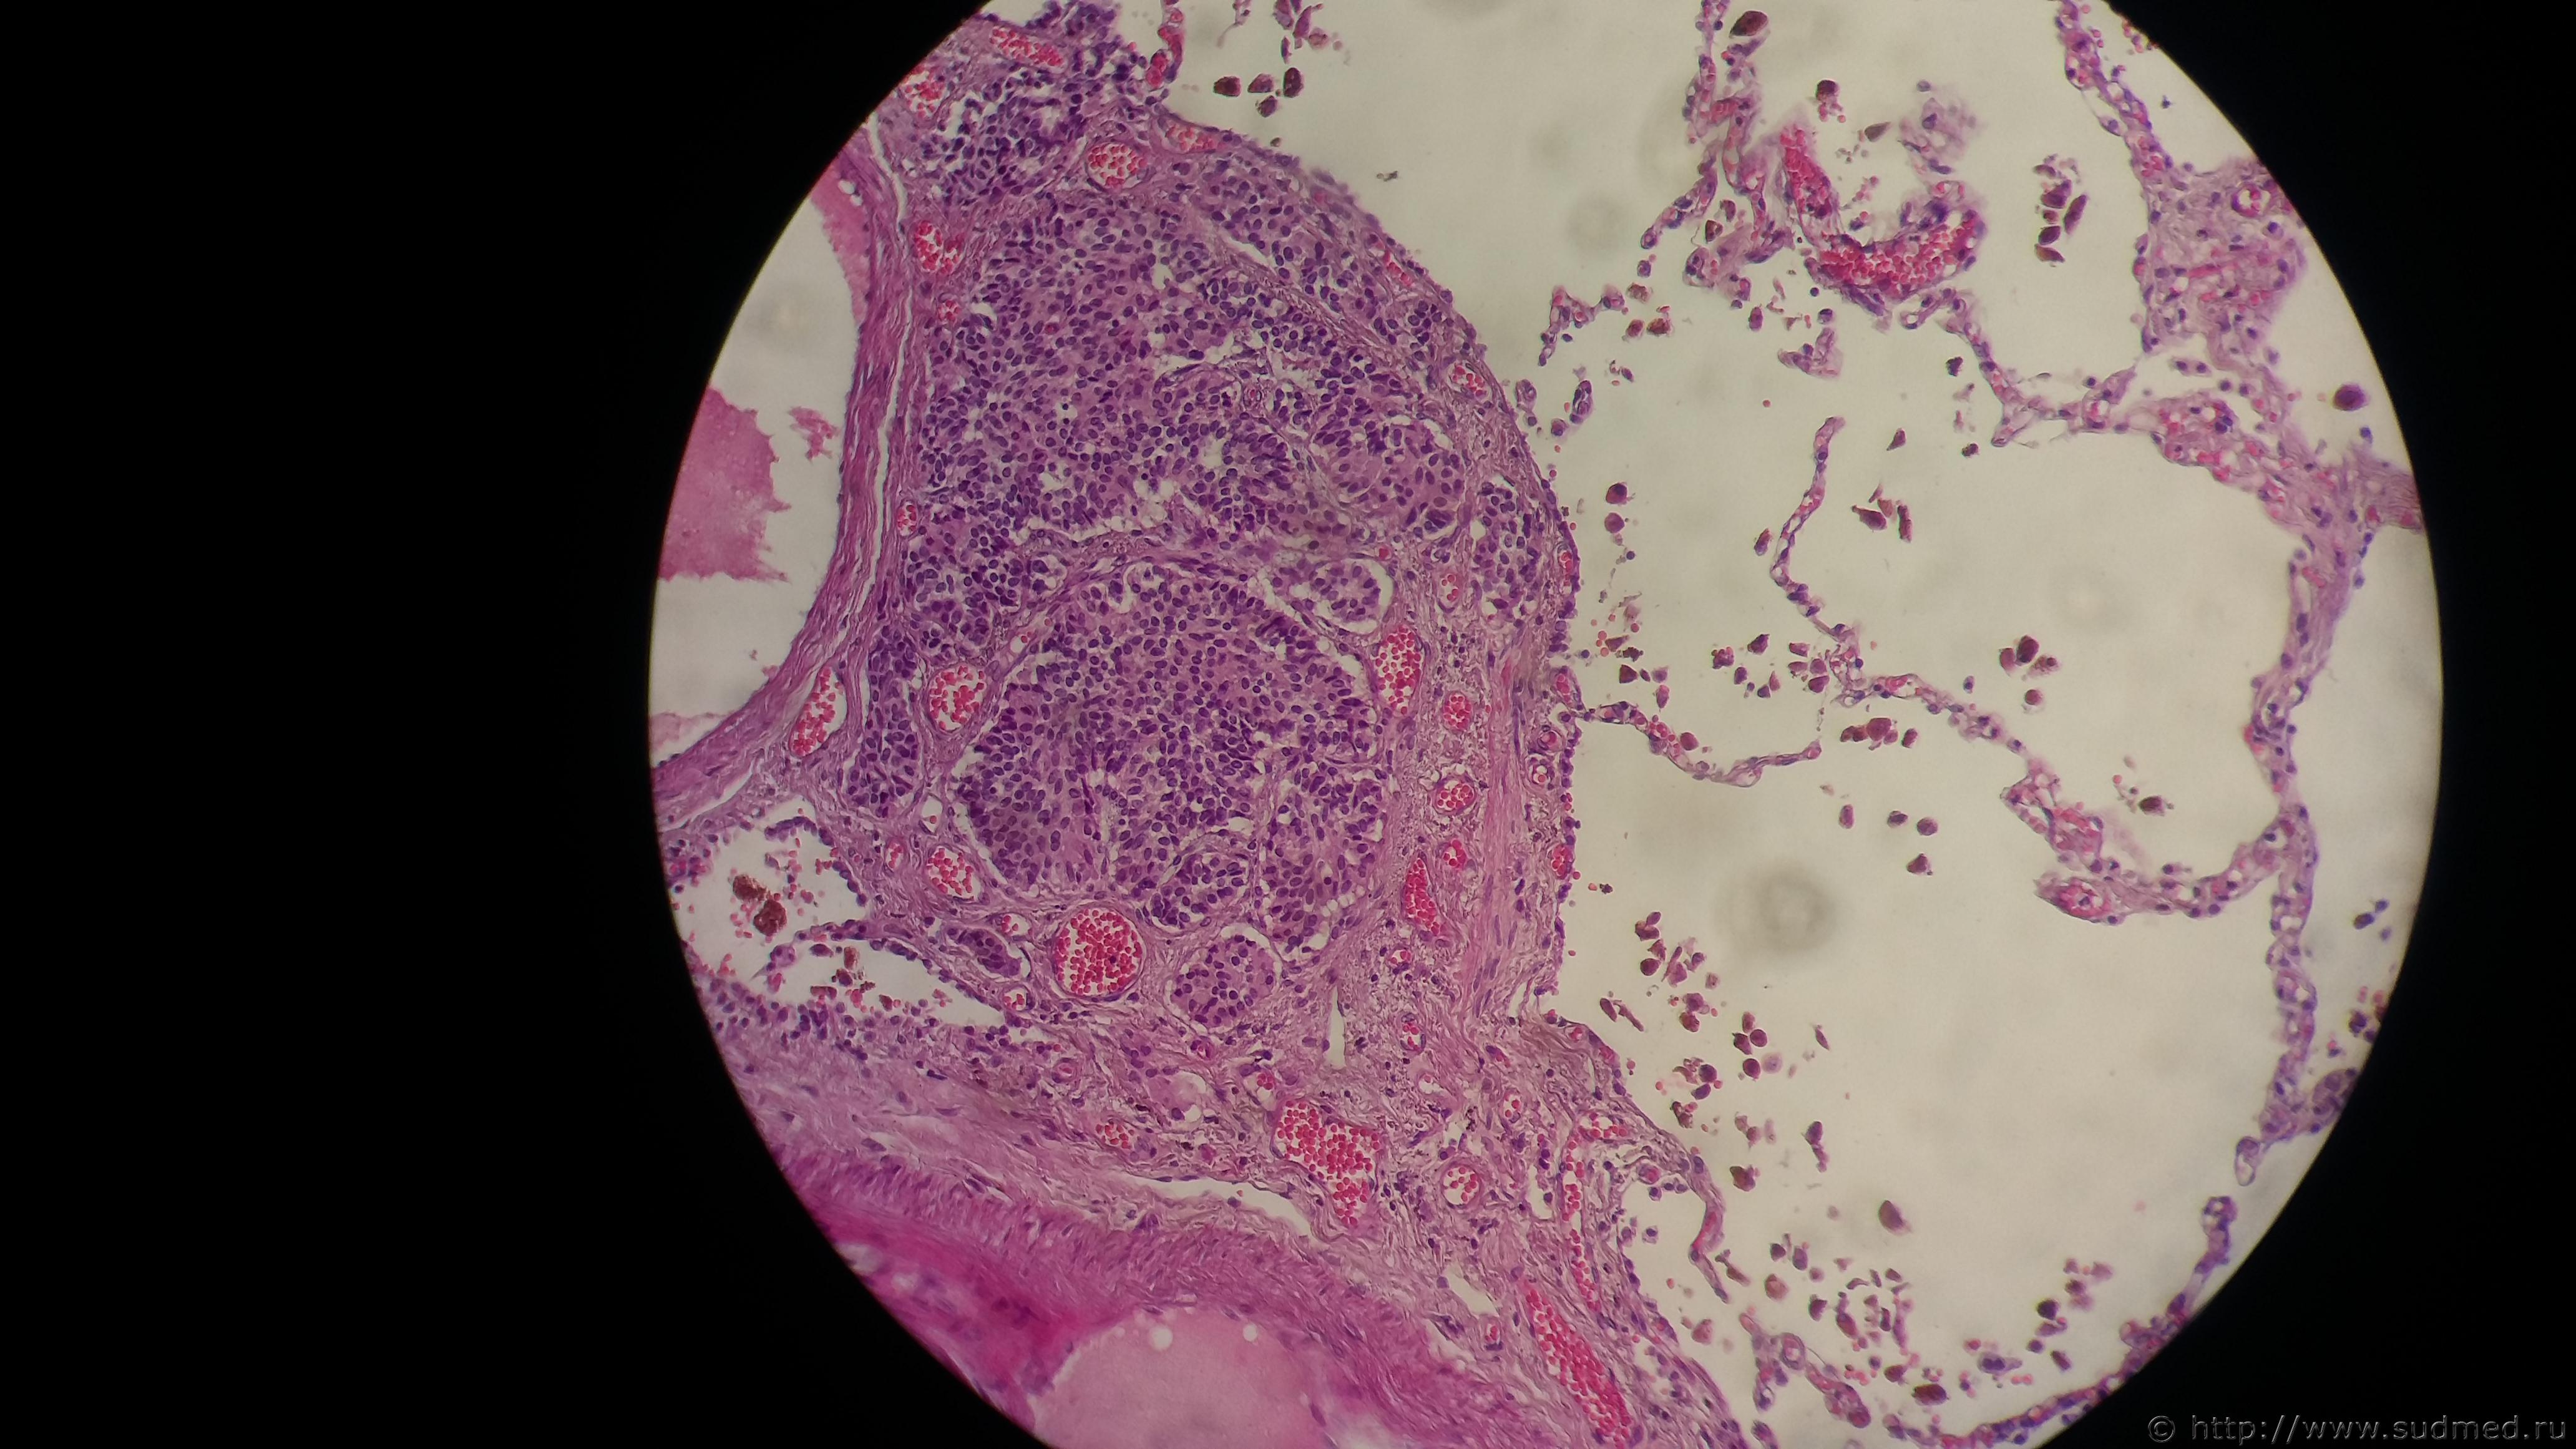

Новорожденный , жил 3 дня. После родов получил травму головы в неизвестных обстоятельствах. Ушиб головного мозга. В мягкой ткани головы затылочно-теменной области кровоподтеки 3х4см. Осложнение ДВС-синдром . Кровоизлияние в головном мозге, геморрагии в алвеолах с аспирацией в просвет бронхов. Судебная медицина - Прикрепленное изображениеСудебная медицина - Прикрепленное изображениеСудебная медицина - Прикрепленное изображениеСудебная медицина - Прикрепленное изображение